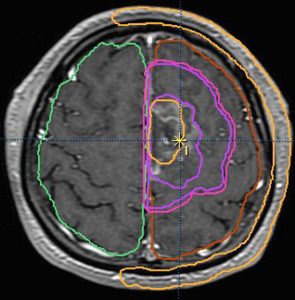

放射線治療計画(照射野)と脳にあたる放射線の量の簡単な図での説明

オレンジの色がGTVではっきり腫瘍と断定できるところです

グリオーマはMRIでみえる以上に広がっているので,腫瘍の周囲を十分に囲む領域を照射します,それを臨床的標的体積 (CTV)といいます

赤紫の線で囲った部分の内側で,びまん性グリオーマの場合は,GTVから20mmくらいの距離を取るのが普通です

さらに少し (0.3-0.5cm) 領域を広げてかけ損じのないようにするので治療計画表的体積 (PTV)といいます,上の図では赤紫の2本の線の外側にあたります

薄茶色に塗った部分には計画54グレイの90%以上の線量が入ります

この体積の決め方は腫瘍の形や悪性度によっても変わってきます

放射線治療医の腕の見せ所です

実際に放射線があたるのはPTVの領域です

この例の治療計画でとても大切な点は,腫瘍のある左前頭葉には放射線が十分入っているのですが,右前頭葉の被曝は最低限に抑えられている点です

両側の前頭葉の対照的な被曝では認知機能が著しく低下することを知っている放射線治療医だからできることです